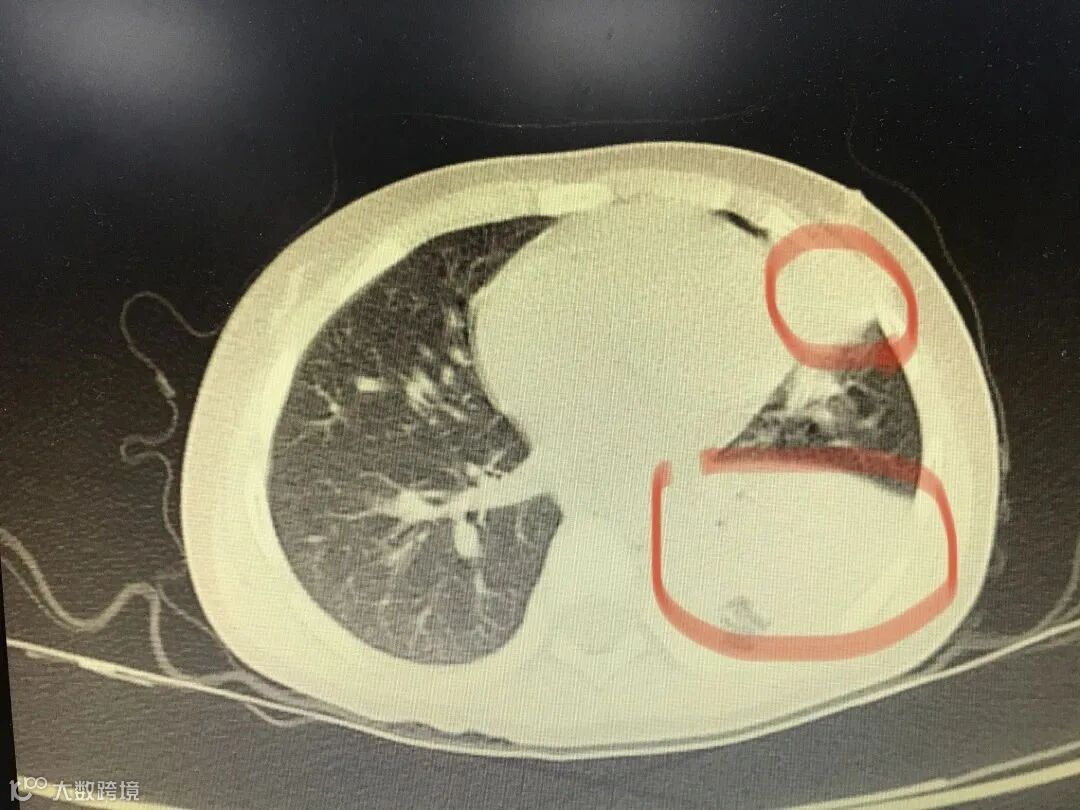

收入院后女孩仍呈高烧状态,在吸着氧的状态下监测指脉氧不理想。查肺部CT发现女孩的左肺几乎呈现白色,就是大家通常称的“白肺”,也就是说女孩左边肺部几乎被异物完全堵住,只能靠右肺呼吸。

医生花费了70分钟从女孩的左肺支气管里取出了很多痰栓,部分呈现为树枝状痰栓,医学上称塑形性支气管痰栓,最长的接近3厘米,短的则有1-2厘米,从肺部里洗出的大多数是块状的痰。